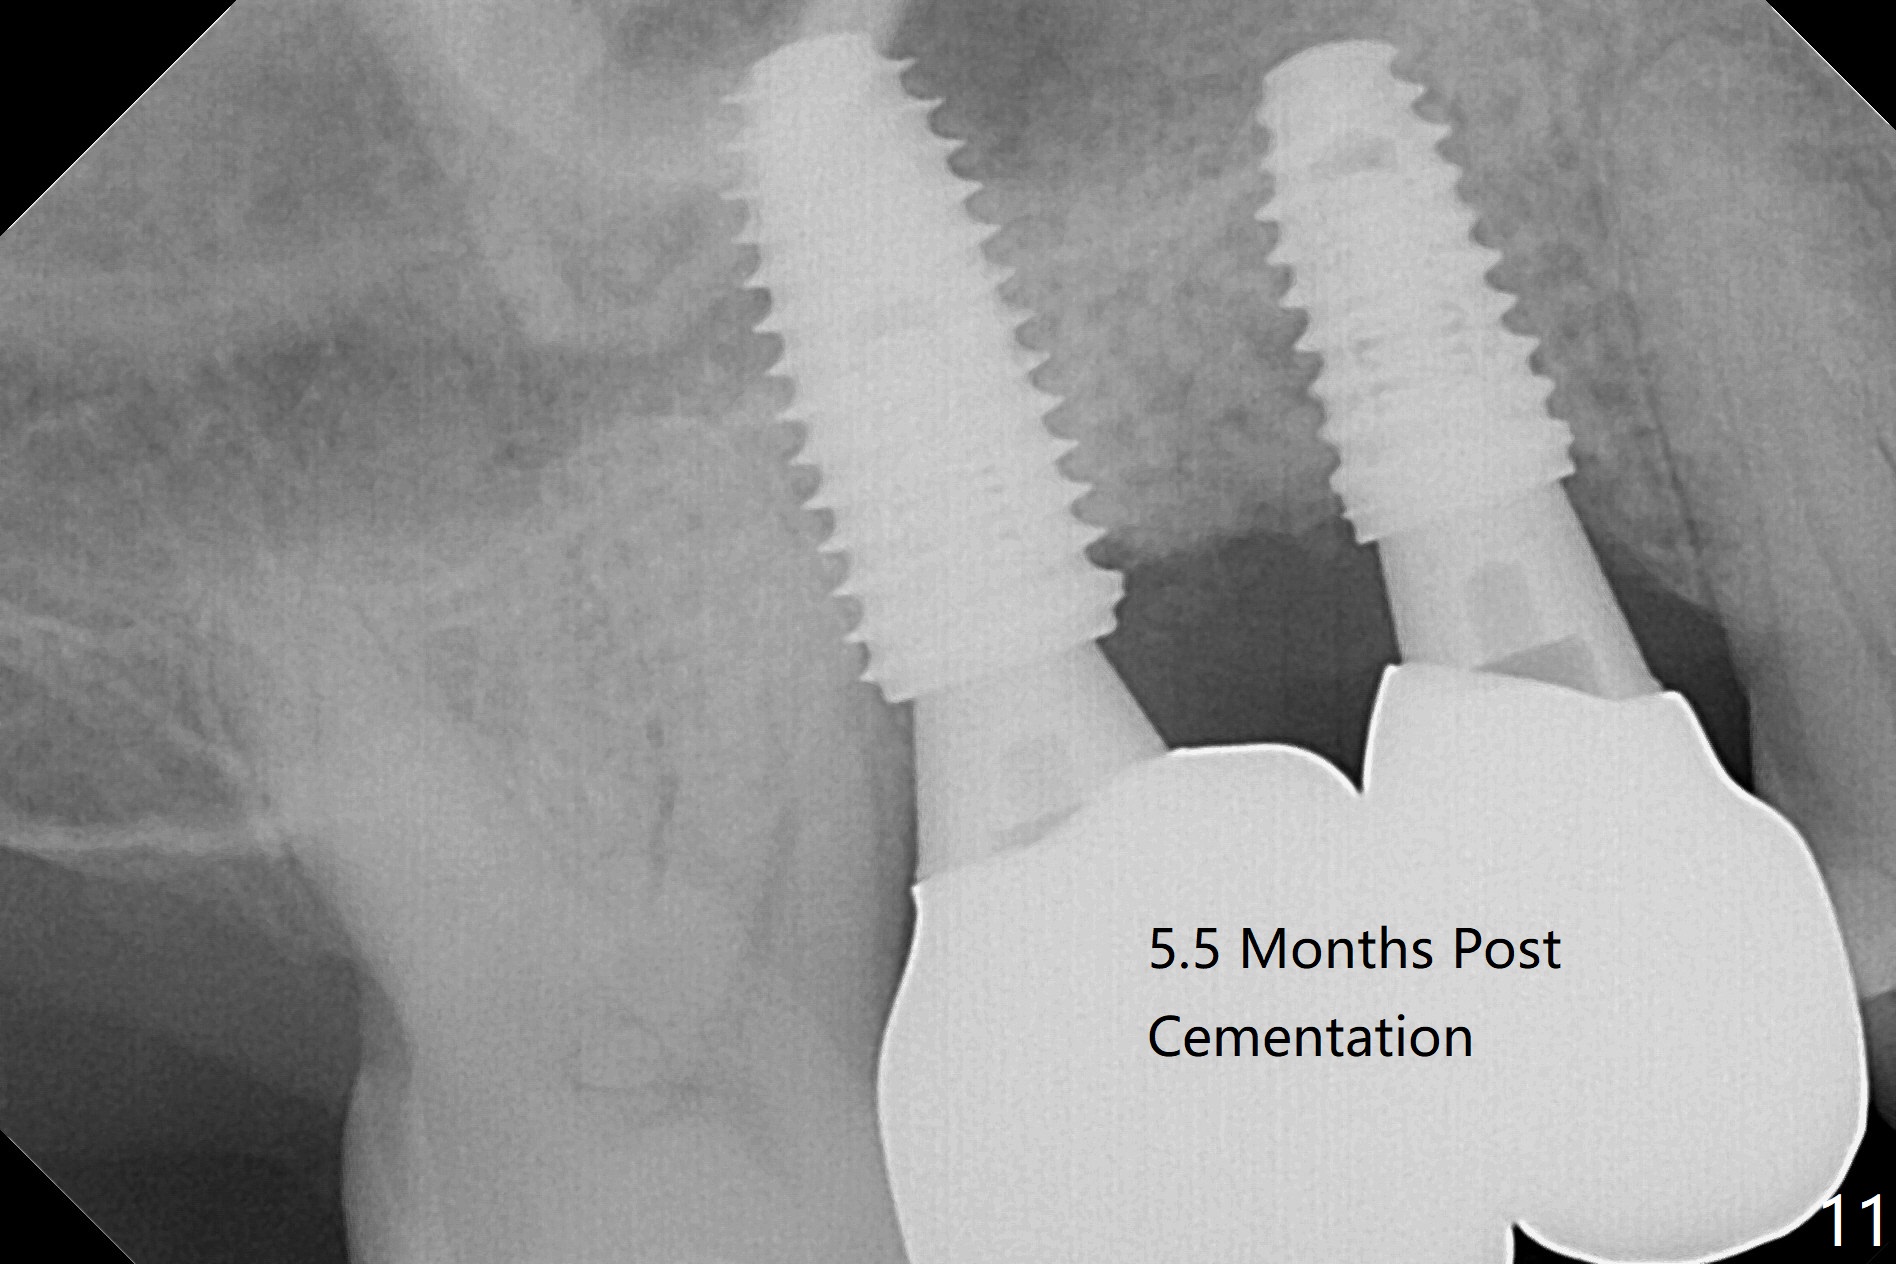

When the tooth #3 with severe buccal gingival recession is extracted and implants are placed at #3 and 4 with guide, sticky bone in 2 large pieces is packed between these implants with a previously large defect in a seemingly secure manner (Fig.1 *). Use of a longer implant at #3 (11.5 mm vs. 10 mm) will reduce the chance of abutment screw loosening in the future. With 2 pieces of PRF membrane coverage, an immediate provisional is fabricated for graft retention (Fig.2,3 P). To stabilize a buccal flap (Fig.2 *, used to be buccal furca gingiva), periodontal dressing is applied later. The buccal socket heals 12 days postop (Fig.4). Apparently new bone forms between the implants 4 months postop (Fig.5). The abutment at #3 may not be completely seated. In fact it is loose, probably related to buccal gingival and gingival cuff erythema 6.5 months postop (Fig.6). Large healing abutments are placed to form the interdental (interimplant) papilla without effect (*). Provisional crowns will be fabricated for the papilla formation. When cemented abutments are placed (Fig.7), papilla formation by manipulation of provisional crowns seems unlikely. Impression is taken. Although there is no implant thread exposure, the buccal plate is concave 7.5 months postop (Fig.8). With special crown design, food impaction should be minimal post cementation (Fig.9,10). There is no bone loss 5.5 months post cementation (Fig.11), while the soft tissue is healthy (data not shown).